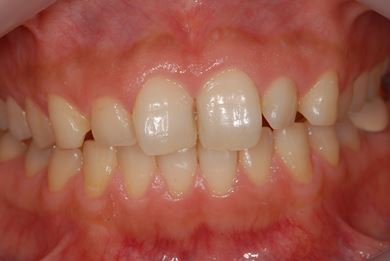

インプラントの症例写真 IMPLANT

インプラント治療+セラミック治療+歯肉歯槽骨整形

| 性別/年齢 | 女性 / 38歳 | ||||||||||||||||||||||||||||||||

| 主訴 | 右下奥の欠損のため、インプラントを希望。また、左に物が挟まりやすいための治療も希望。 | ||||||||||||||||||||||||||||||||

| 治療内容 | インプラント1本、ジルコニアフレームオールセラミッククラウン2本(ジルコニアセラミック用土台1本)、歯肉歯槽骨整形 | ||||||||||||||||||||||||||||||||